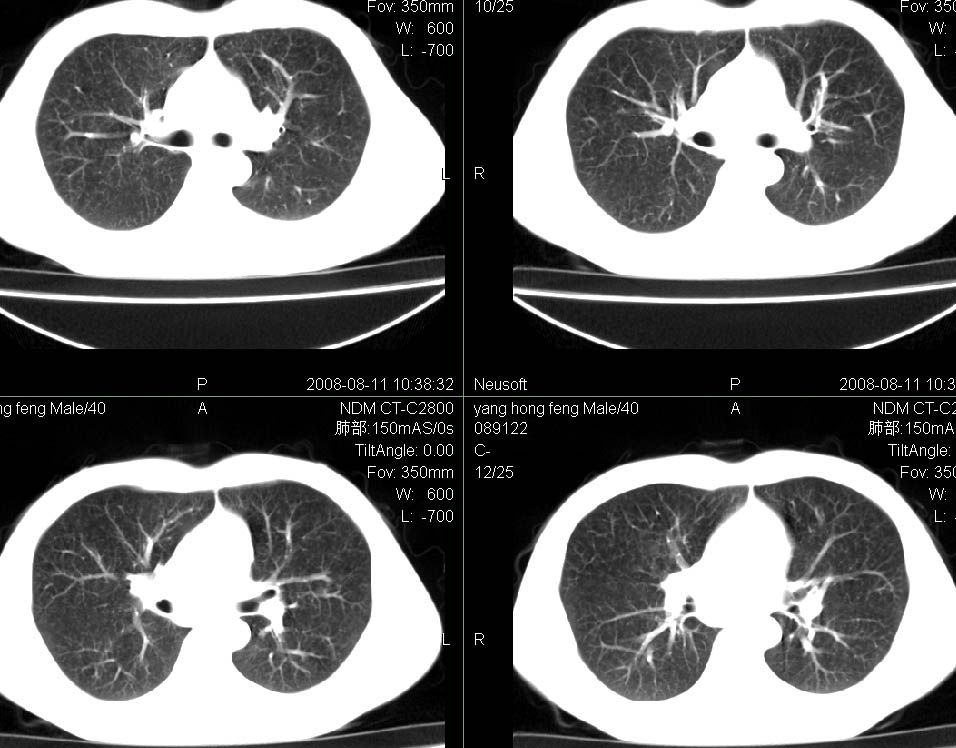

标题: CT15138:男,40,咳嗽胸痛. [打印本页]

标题: CT15138:男,40,咳嗽胸痛.

外院穿刺未见癌细泡,结核菌素实验阳性,未正规治疗2个月复查病灶及纵隔淋巴结增大

结合病史及临床表现考虑右侧中心型肺癌纵隔转移,

考虑周围型肺癌可能性大

右侧中心型肺癌纵隔转移!

右肺中叶肺癌,纵隔淋巴结转移.

考虑   右肺中叶肺癌,纵隔淋巴结转移.建议穿刺活检。炎性假瘤待排

考虑右肺中叶周围型肺癌并纵隔淋巴结转移。